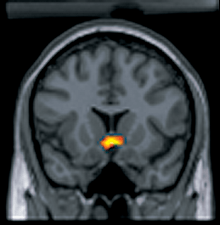

Mapping and lesion studies on BSR were designed to determine the location of reward-relevant neurons as well as determine the signal pathways that are directly affected by brain stimulation. The site of intracranial self-stimulation leads to substantially different behavioral characteristics. Sites along the length of the medial forebrain bundle (MFB) through the lateral and posterior hypothalamus, the ventral tegmental area (VTA), and into the pons are associated with the strongest reward effects of stimulation.[1]

The lateral hypothalamus is a portion of the hypothalamus, and brain stimulation to this area of the reward system produces the highest response rates and subsequently the highest reward potency. Lesions in this region or along its boundary cause a loss of positive drive-reward behaviors as well as all other operant drive behaviors.[8]

The medial forebrain bundle (MFB) is the location of the most frequently investigated brain stimulation reward sites, and it is composed of a complex bundle of axons coming from the basal olfactory regions and the septal nuclei.[3] MFB is not the sole anatomical substrate responsible for reinforcing brain stimulation; however, it is the main pathway for the ascending dopamine fibers and it functions to relay information from the VTA to the nucleus accumbens. The rewarding effect of the MFB depends on the ability of the stimulation to activate the mesocorticolimbic dopamine system.[1]

The mesolimbic pathway contains the VTA, nucleus accumbens, amygdalae, and the medial prefrontal cortex. The nucleus accumbens is a part of the striatum that integrates information from cortical and limbic brain structures to mediate behaviors the reinforce reward .[13] The nucleus accumbens is a major target for the dopaminergic projections from the brainstem that are associated with BSR. The VTA is a group of neurons located close to the midline on the floor of the midbrain, and VTA is the origin of dopaminergic cell bodies that comprise the mesocorticolimbic dopamine system.[3]